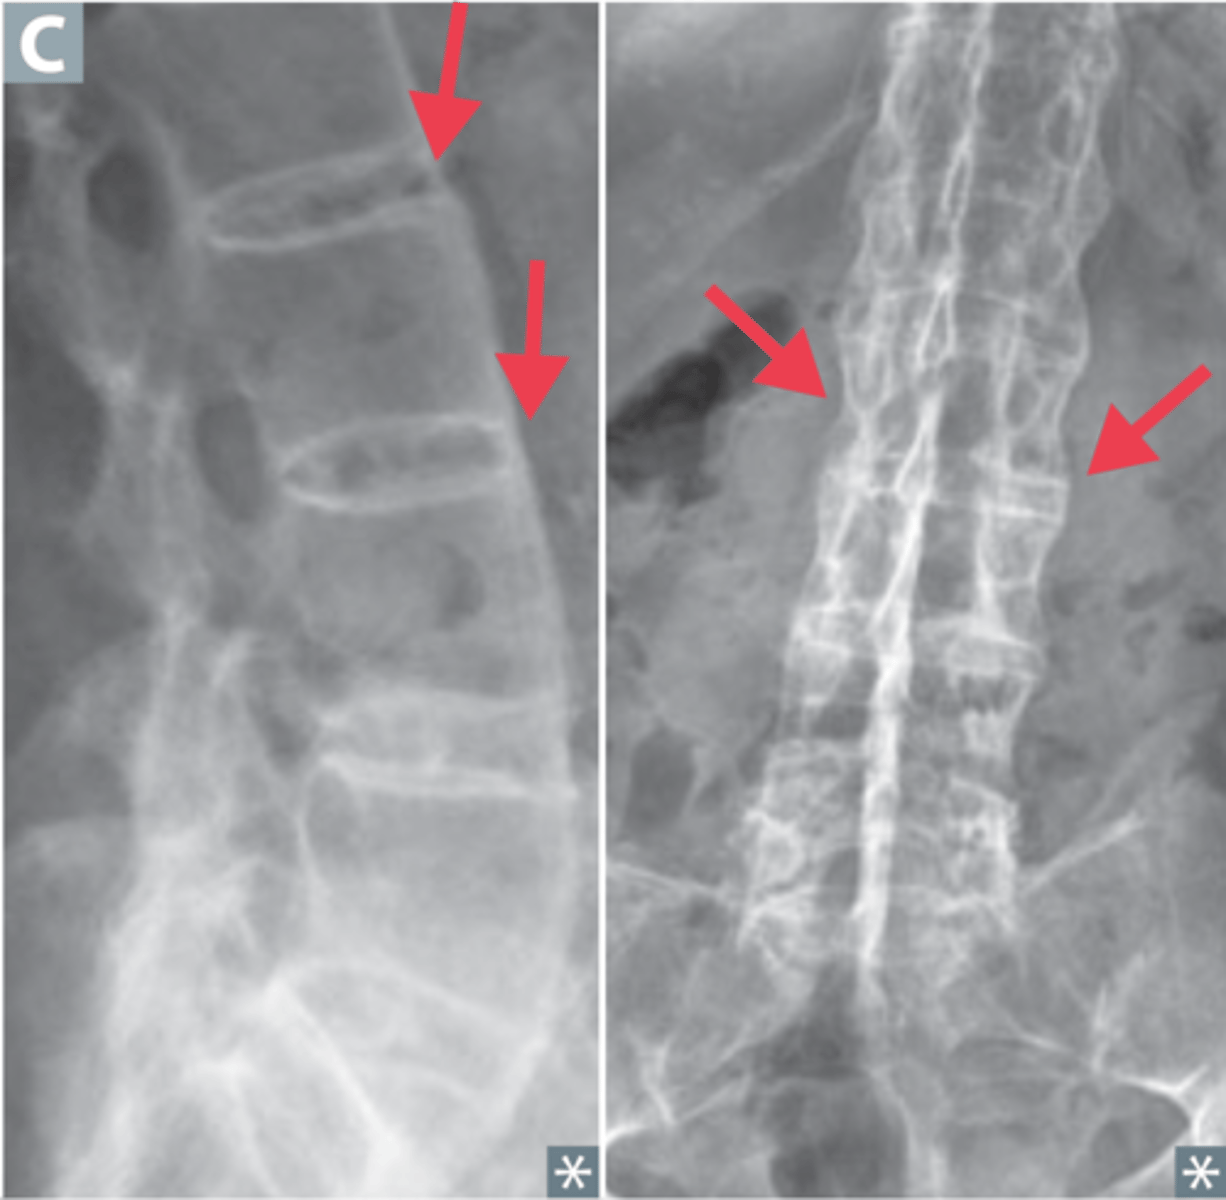

Bamboo spine

AS finding

Spine - fusion in ascending manner, kyphosis, reduced mobility, "bamboo spine", question mark posture

- Imaging of back = bamboo spine